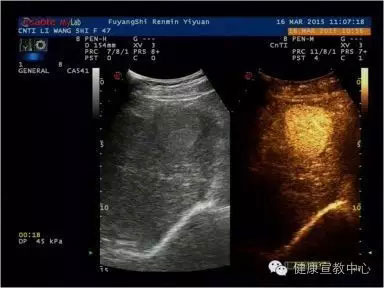

(甲乳分級(jí)診斷彈性評(píng)估技術(shù))

(超聲造影輔助分類)

(肝臟超聲造影)